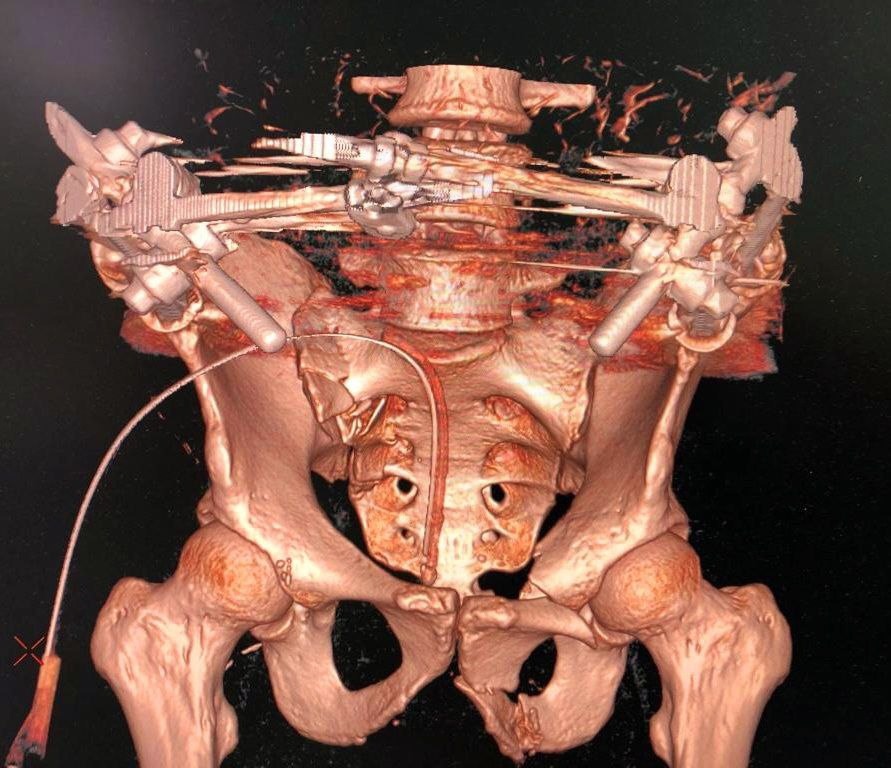

Мужчину 46 лет доставили в аппарате наружной фиксации, так как такой перелом являлся угрозой для жизни пациента в связи с опасением образования обширных гематом и жировой эмболии. В травматологическом отделении Александру была проведена компьютерная томография, в результате которой диагностировали: разрыв крестцово-подвздошного сочленения и перелом лонных костей таза.

Была проведена сложная операция по восстановлению тазового кольца и остеосинтез костей таза. После успешно проведенного хирургического вмешательства пациент в скором времени сможет передвигаться без ограничений.